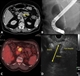

Maintain a high index of suspicion for kidney cancer

25 Apr 2022

More than 50% of renal cell carcinoma (RCC) cases are detected incidentally on imaging, often at a late stage. Patients may present with mass-related localised symptoms, constitutional symptoms and symptoms of metastatic disease. Ultrasound is the optimal initial investigation to screen individuals with suspected RCC. NICE recommends that patients aged 45 and over with isolated haematuria, in the absence (or following treatment) of a urinary tract infection, are referred for investigation of a potential renal malignancy.